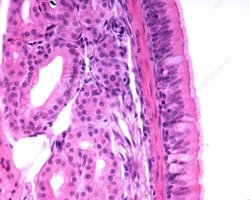

Histology of the Respiratory Tract

Respiratory Mucosa

The respiratory mucosa lines the conducting portion and consists of an epithelial layer and a deeper lamina propria. It contains mucous glands and, in some regions, smooth muscle.

Types of Respiratory Epithelium

Pseudostratified ciliated columnar epithelium: Nasal cavity, nasopharynx, superior lower respiratory tract

Stratified squamous epithelium: Inferior pharynx, oropharynx, laryngopharynx

Cuboidal epithelium: Smaller bronchioles

Simple squamous epithelium: Alveoli (site of gas exchange)